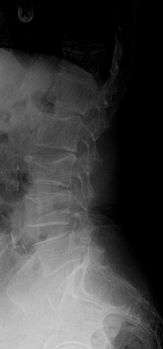

Compression fracture of the fourth lumbar vertebra post falling from a height.